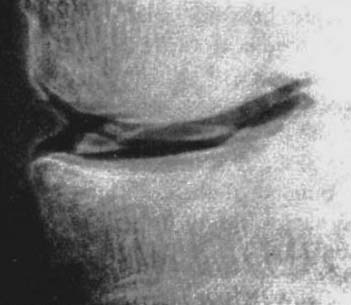

図7. 男児.舟状骨の硬化像

【要旨・解説】足の舟状骨の骨端症,いわゆるKöhler病の初報である.症例は5~9歳の男児3例で,いずれもX線写真で舟状骨に高度の硬化性変化が認められた(図7).うち1例は両側性で,なおかつ両側膝蓋骨にも同様の変化が見られた.当時このような疾患は報告がなく,未知の新しい疾患と思われるが,比較的短期間に3症例を経験したことから比較的多い疾患であろうとも述べている.成因として,クレチン病,蒙古症,くる病,淋病,梅毒,結核などの可能性を検討し,そのいずれもあてはまらずその後の検討を待つとしている.Köhler病をふくめ骨端症の成因については現在も不詳の点が多いが,発育期の骨に対する軽微な外傷,ストレスによる虚血性壊死が主因と考えられている.特に舟状骨に好発する理由として,舟状骨の骨化が他の足根骨に比して遅いことが関連している可能性をvon Recklinghausenに指摘されたとの記載があり,正鵠を射たものと言えよう.

現在,Köhler病という名称は主に足の舟状骨の骨端症をさして用いられるが,この初報に膝蓋骨病変の合併が記載されていることから膝蓋骨の骨端症についてもこの名称が用いられることがある(膝蓋骨の骨端症としては,膝蓋骨下端の二次骨化中心に発生するSinding-Larsen-Johansson病があるが,Köhler病は膝蓋骨中央部の一次骨化中心の病変をさす).